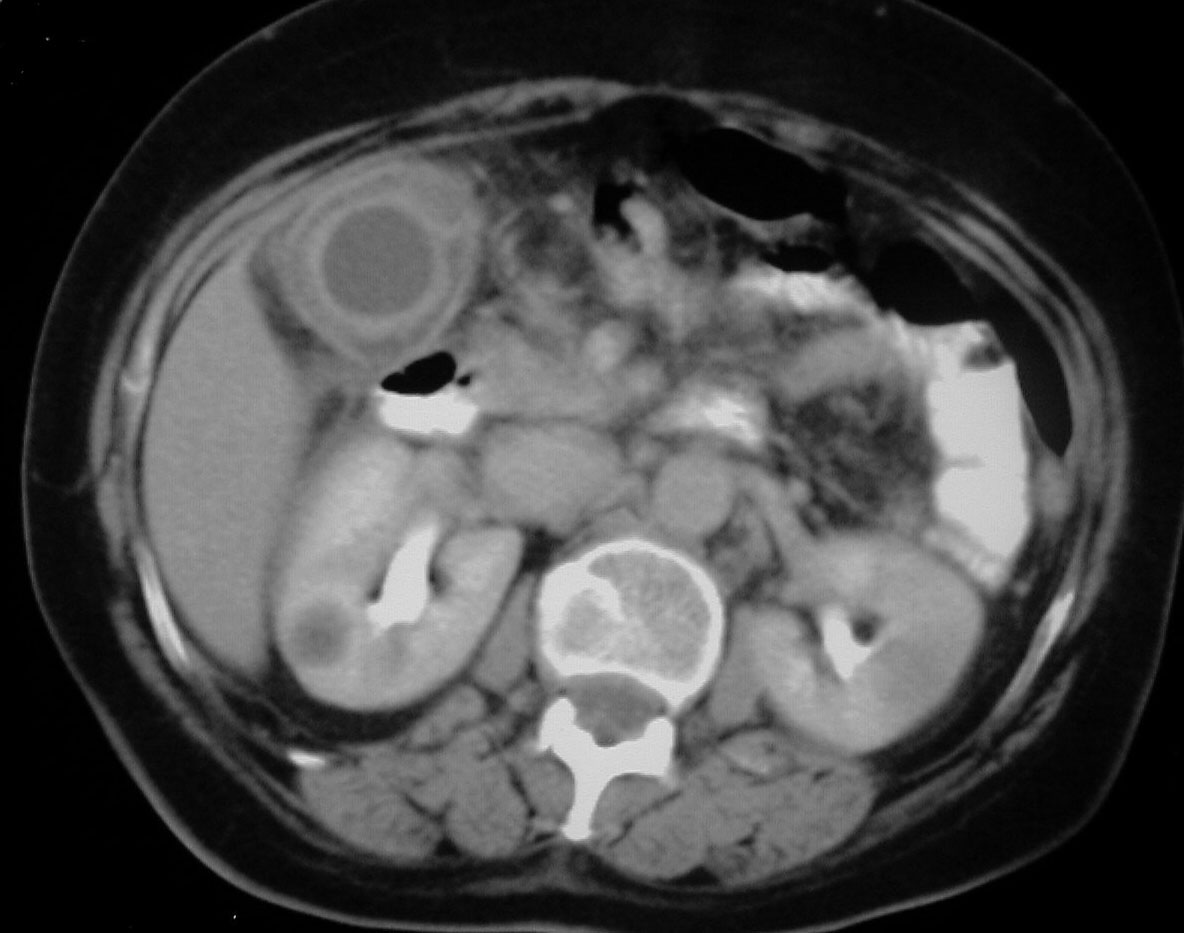

SIGNO DE LA ESCOPETA o CANAL PARALELOescopeta1Signo clásico en ecografía de dilatación de la vía biliar intrahepática. Un conducto biliar dilatado –flecha roja- corre paralelo a la rama portal acompañante –flecha blanca-, con calibre similar, dando una imagen de escopeta de doble cañón.escopeta2Corte axial de TC de abdomen del mismo paciente, que muestra dilatación biliar intrahepática donde puede verse una imagen similar al signo ecográfico (círculo).escopeta3Un corte más caudal muestra una masa en la cabeza del páncreas (flechas rojas) causante de la dilatación biliar (flecha blanca).